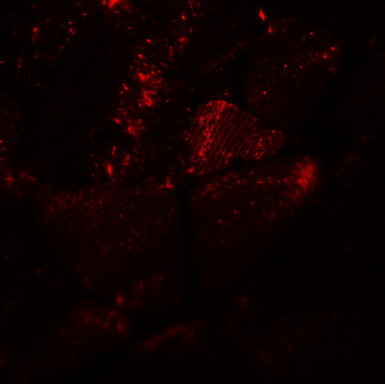

Supportive validation

- Submitted by

- OriGene (provider)

- Main image

- Experimental details

- Immunofluorescence of MYH8 in mouse skeletal muscle tissue with MYH8 antibody at 20 ug/mL.

- Validation comment

- IF